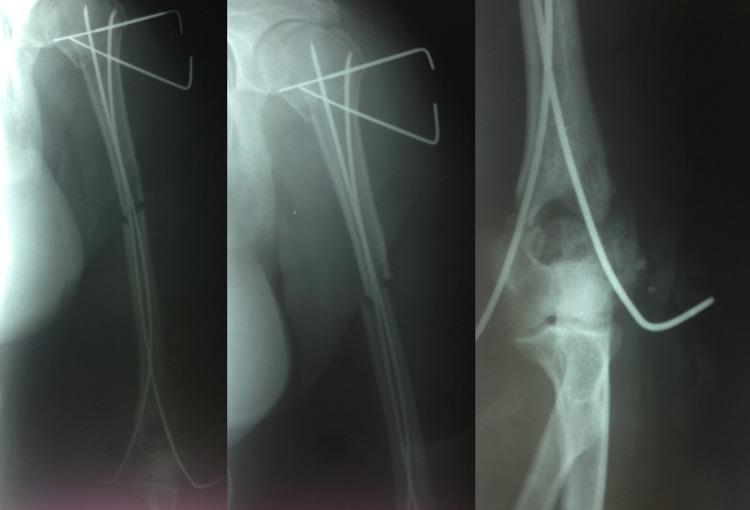

A polytrauma patient with a life-threatening condition is a quite demanding situation due to special considerations regarding the time, the way, and the sequence of the necessary procedures. Elastic intramedullary nails (EIN) could be used under these conditions for adult patients with humeral fractures requiring fixation. Here we present a case of a multi-segmental closed humerus fracture in a polytrauma patient treated by EIN. The general condition of the patient and the need for multiple surgical procedures required the selection of a minimally invasive and time-saving fixation technique. The patient's follow-up was uneventful with complete healing of the humeral fracture; the functional scores results are excellent at five years post operatively. A review of the literature revealed limited published cases of humeral fractures (128 patients) treated by EIN, despite the fact that the results are quite encouraging. Based on our results and the current literature, we believe that EIN could become an effective treatment choice for multi-level humerus fractures, especially in damage control surgery.

对于一名有生命危险的多发伤患者而言,由于在时间、方式以及必要手术步骤顺序方面存在特殊考量,这是一种要求颇高的情况。在这些条件下,弹性髓内钉(EIN)可用于需要固定的成年肱骨骨折多发伤患者。在此,我们呈现一例多发伤患者的多节段闭合性肱骨骨折,采用EIN进行治疗。患者的总体状况以及需要进行多项外科手术,这就要求选择一种微创且节省时间的固定技术。患者的随访过程顺利,肱骨骨折完全愈合;术后五年的功能评分结果极佳。文献综述显示,尽管结果颇为令人鼓舞,但已发表的采用EIN治疗肱骨骨折的病例有限(128例患者)。基于我们的结果以及当前文献,我们认为EIN可能成为多级肱骨骨折,尤其是在损伤控制手术中的一种有效治疗选择。